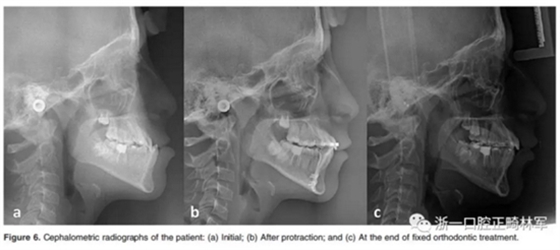

在開合關(guān)閉后,并用直絲弓技術(shù)繼續(xù)治療。在固定正畸治療過程中,有5位患者拔除上頜前磨牙,以解除擁擠和II類尖牙關(guān)系。對于正在生長發(fā)育的III類患者夜間佩戴bianator。治療前后拍攝頭顱側(cè)位片。Figure 5和Figure 6顯示了該組中的一名患者的治療過程。

6.jpg

7.jpg